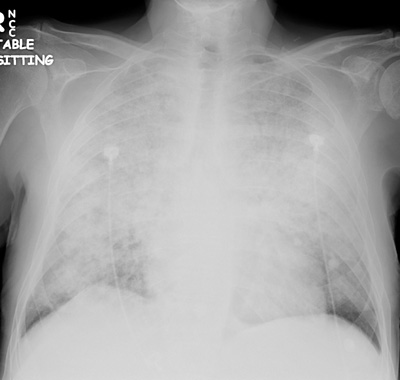

ARDS CXR for when patient is hypoxic found here:

(CXR source: http://www.radiology.vcu.edu/programs/residents/quiz/pulm_ cotw/PulmonConf/09-03-04/68yM%2008-03-04%20CXR.jpg)